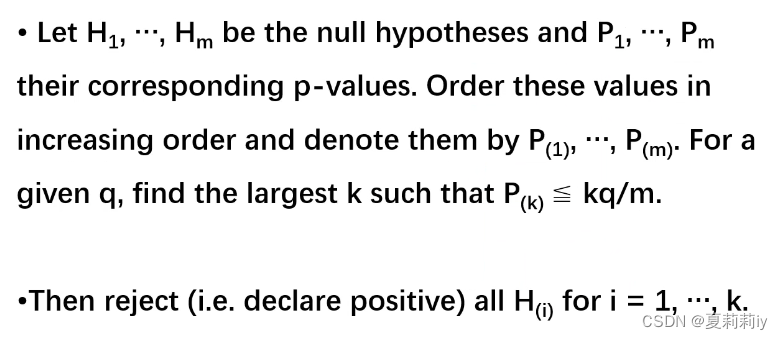

2.2. 多重比较矫正(Multiple Comparison Correction)

②False Discovery Rate(FDR):有很多种方法(太多且复杂就不一一例举,仅给出严老师PPT里给的方法),比Bonferroni更为温和实用。在DPABI_VIEW里Cluster可选FDR矫正